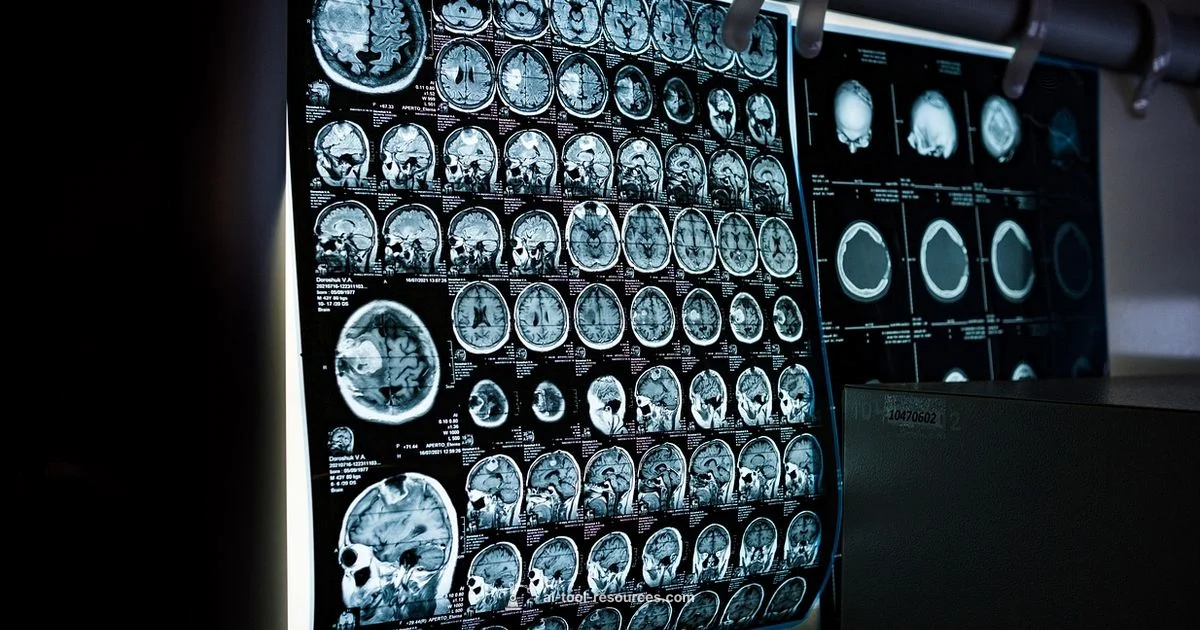

Why AI Tools for X-Ray Analysis Matter in Modern Healthcare

The field of radiology is being transformed by AI, and the keyword ai tool for x ray analysis has moved from novelty to necessity. In busy clinics and research labs, AI assists radiologists by spotting subtle patterns, prioritizing urgent cases, and standardizing findings across devices. According to AI Tool Resources, selecting an ai tool for x ray analysis requires balancing accuracy, speed, explainability, and regulatory compliance. The best solutions integrate seamlessly with existing DICOM workflows, support clinician oversight, and provide transparent reasoning for their detections. When you evaluate tools, look for models trained on diverse patient sets, robust validation protocols, and clear audit trails. This block introduces the landscape without promising magical results; the actual value comes from disciplined evaluation and real-world testing. Expect improvements in triage times, reduced reading fatigue, and better consistency across radiologists when the tool is properly integrated. In this guide, we explore practical criteria, typical features, and how to pick an ai tool for x ray analysis that truly fits your lab’s needs.